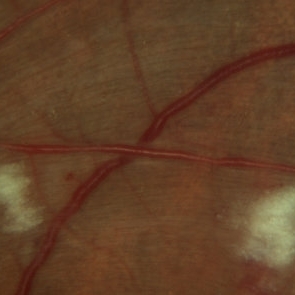

Arteriovenous Nipping, Cotton Wool Spots

Mar 1 2014 by Homayoun Tabandeh, MD, FASRS

Arteriovenous nipping, cotton wool spots in a patient with hypertensive retinopathy and diabetes

Condition/keywords: cotton wool spots